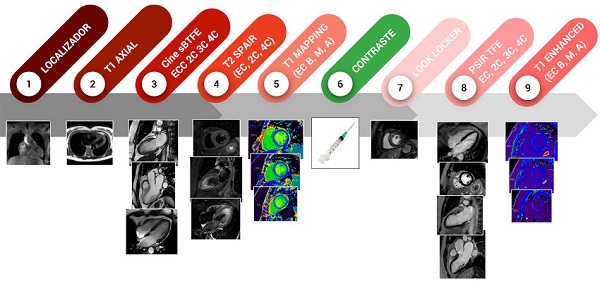

Estudio RMC

Se realizaron todos los estudios siguiendo estrictamente los protocolos nacionales e institucionales de control de infecciones. Se utilizó un resonador magnético de alto campo Philips Ingenia® V5 de 3.0T (Philips Healthcare, Holanda) equipado con paquete cardíaco avanzado incluyendo tecnología de shimming del campo magnético con radiofrecuencia (MultiTransmit). Se colocaron electrodos de carbono, no ferromagnéticos, para obtener imágenes gatilladas con el electrocardiograma (ECG). Se colocó sobre el tórax una antena de superficie de múltiples detectores. Las imágenes anatómicas axiales se obtuvieron con secuencia de sangre negra (T1-Single Shot TSE). Para las imágenes T1 y T2 Stir se utilizaron secuencias de turbo spin-echo. Las imágenes de cines se realizaron con secuencias Balanced-FFE. Las imágenes post contraste se obtuvieron luego de la infusión de 0,3 mmol/Kg de gadopentato de dimeglumina (Gd-DTPA-Dimeglumina) y de ajustar el TI, con secuencias PSIR TFE. Para la obtención de las imágenes de T1 mapping se utilizó una secuencia Look-Locker modificada (MOLLI), balanced steady state precession, que requiere una apnea breve (aproximadamente 12 segundos); se realizó en tres cortes de eje corto (basal, medioventricular, apical) antes de la administración de contraste. Aproximadamente 10 minutos luego de la administración de contraste se realizó la adquisición de las imágenes de T1-mapping post-contraste, en los mismos cortes de eje corto. Se programó con los siguientes parámetros: TE/TR/flip-angle (FA): 1.02 ns/2.2 ns, tamaño de vóxel 2 × 2 × 10 mm, pasos de codificación de fase n = 166, 11 imágenes de tres inversiones (3 + 3 + 5) con pausas luego de tres latidos antes de la segunda y la tercera inversión y un adiabatic pre-pulse. En la Figura 1 se detalla el protocolo utilizado.